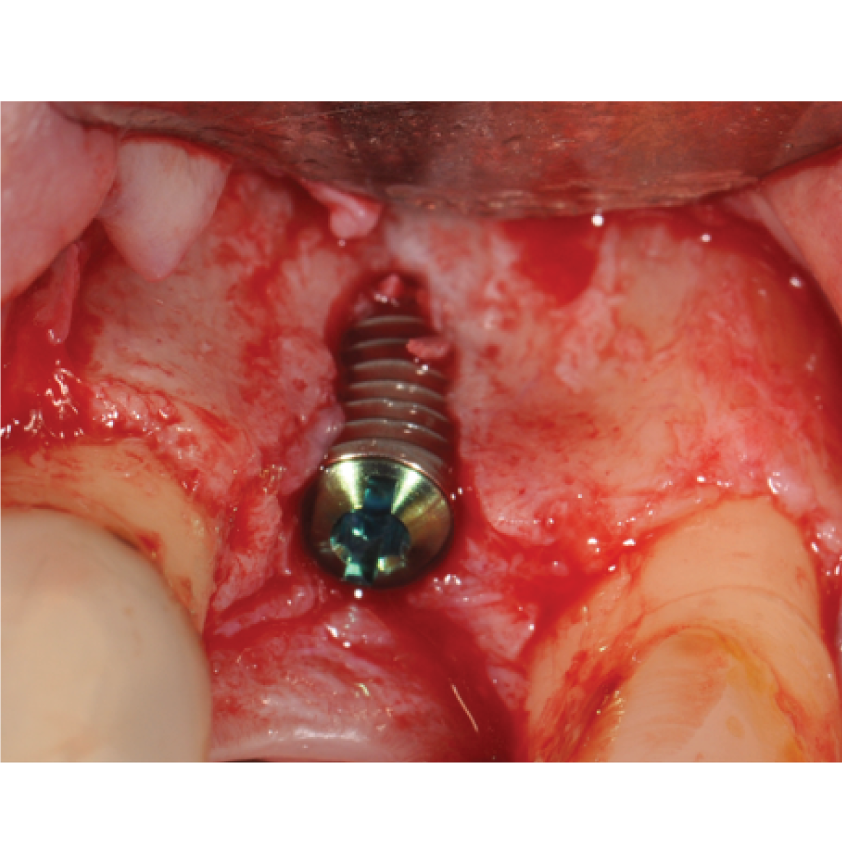

Director’s Clinical Cases

Director’s Clinical Cases